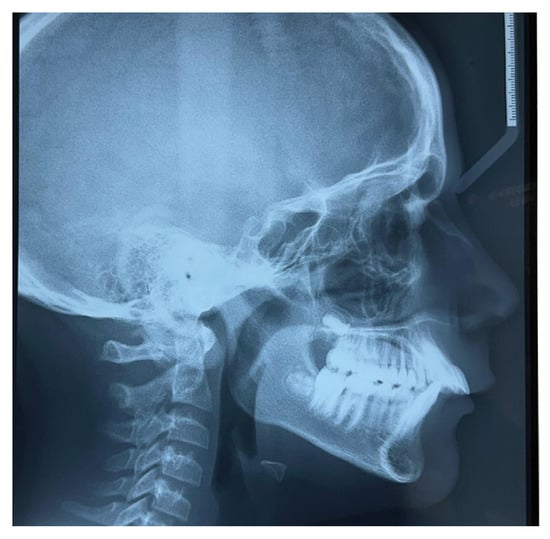

Lateral teleradiography confirmed the skeletal Class II Division I type malocclusion with a mandibular retrusion (Figure 4).

Figure 4.

Lateral teleradiography at T0.